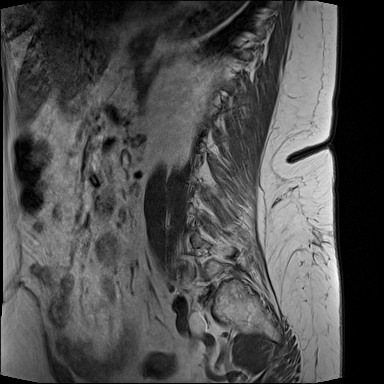

MRT LWS (Lendenwirbelsäule)

DICOM

Magnetresonanztomographie der Lendenwirbelsäule (71 Bilder).

19.01.2024

MRT Lendenwirbelsäule (LWS)

71 Bilder | 1024x1024 px | 15 MB

Januar 2024

MRT LWS + Röntgen Becken

MRT der Lendenwirbelsäule und Röntgen des Beckens zur Diagnostik

MRT mit 71 Bildern